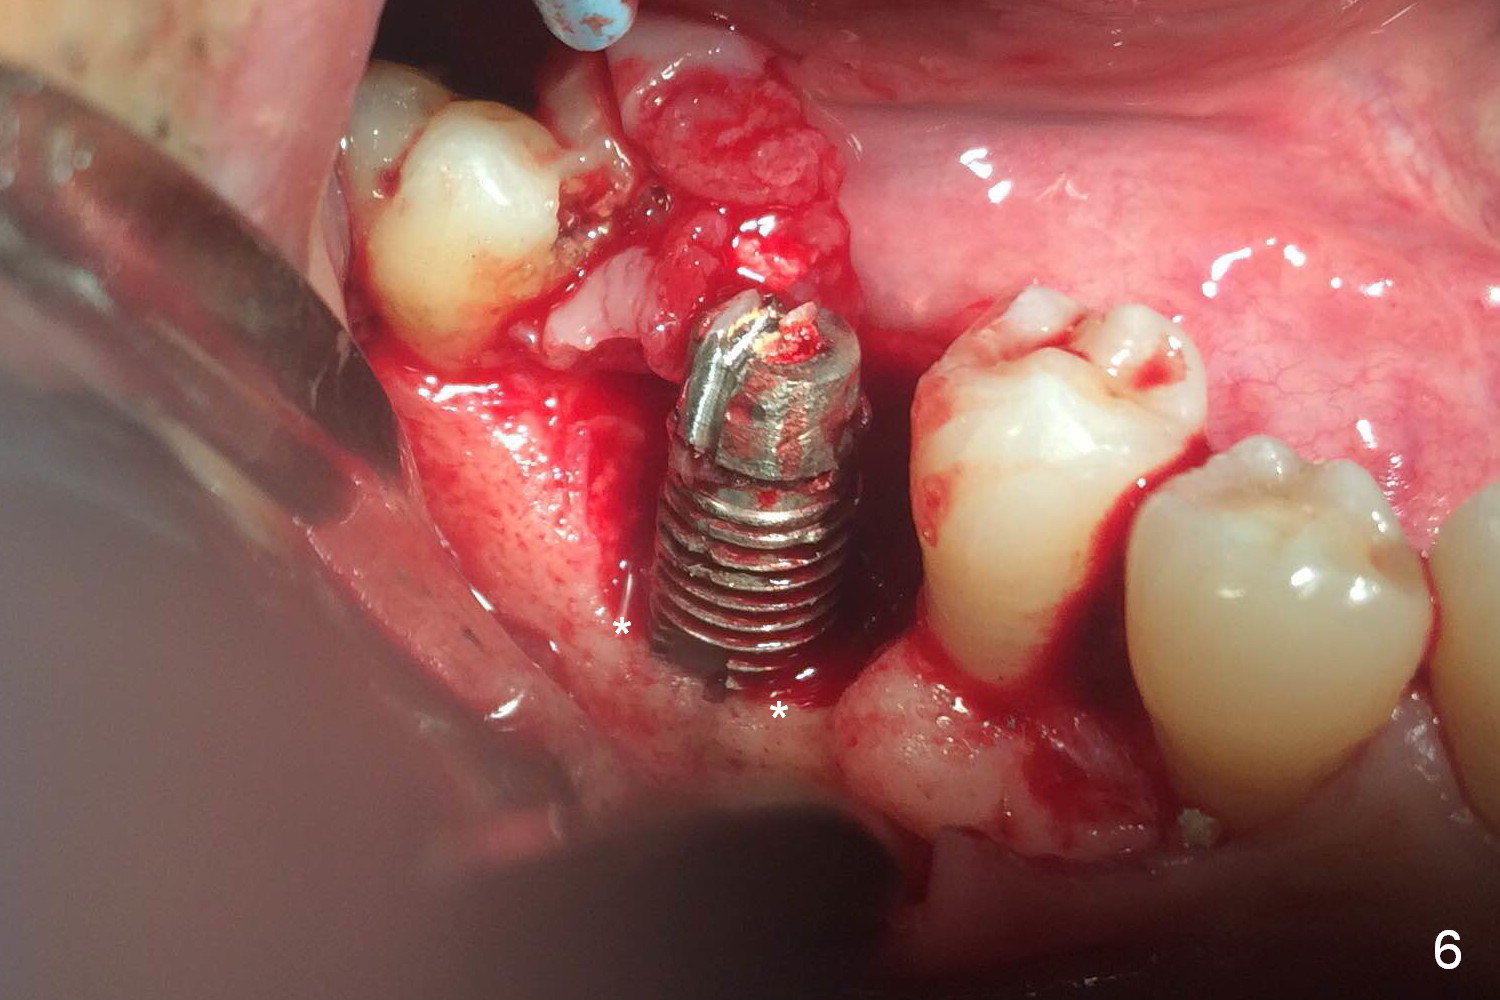

A 49-year-old man develops acute abscess of the lower right quadrant (Fig.3-5) secondary to periimplantitis at #30 (Fig.1,2,6). The latter is probably due to buccal placement (Fig.6 (*: buccal plate)). After removal of the infected implant, an osteotomy is established as lingual as possible using single drill modality (Fig.7 (4.3 mm Magic Drill after 1.6 mm pilot drill and Marking Bur, then Final Drill). With the single drill, the osteotomy does not shift buccally in spite of the lower buccal plate. A 5x9 mm IBS implant is placed lingually as planned (Fig.8 (>40 Ncm)), followed by an angled abutment (5 mm x 15° (4 mm)) (Fig.9 A). The buccal gap is filled with autogenous bone, allograft (.5-1.5 mm) and Osteogen (Fig.10 *), covered by resorbable and non-resorbable membranes. After suturing, periodontal dressing is applied.